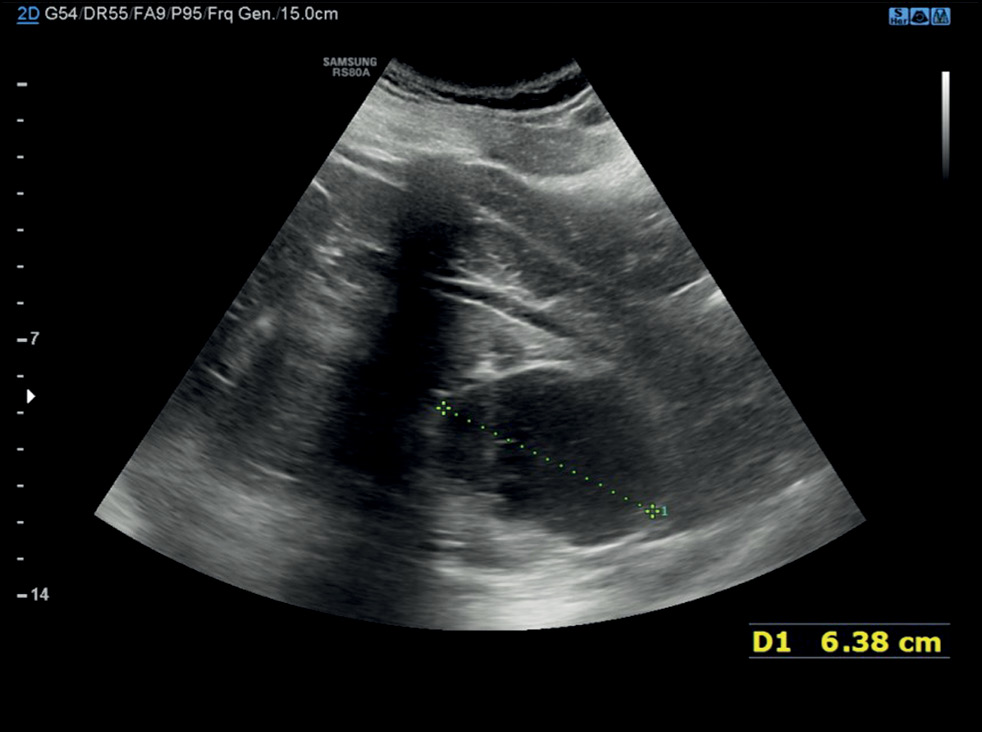

Было проведено ультразвуковое исследование (УЗИ) брюшной полости в качестве обследования первой ступени. В обеих почках визуализировались кисты. Кроме того, в средне-нижней части левой почки визуализировалось крупное образование диаметром около 6,4 см. Эхогенность неоднородная, но преимущественно гипоэхогенно, морфология дольчатая. В связи с опасениями по поводу возможной злокачественности выявленного образования было предложено провести компьютерную томографию (КТ) (рис. 1).

Рис. 1. При ультразвуковом исследовании выявлено неоднородное образование больших размеров, преимущественно анэхогенное, с округлыми чёткими границами, расположенное в средне-нижней части левой почки. Наибольший диаметр составил 6,38 см.